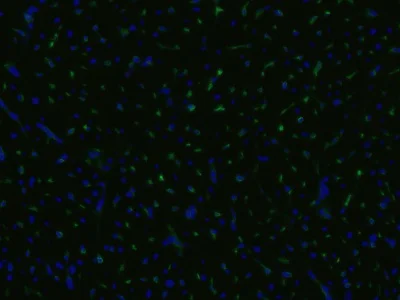

Immunohistochemistry (Frozen sections) - FITC Anti-CD105 antibody [MEM-229] (AB53318)

ab53318 staining CD105 in infarcted porcine heart by Immunohistochemistry (Frozen sections). Cell nuclei were counterstained blue with DAPI.